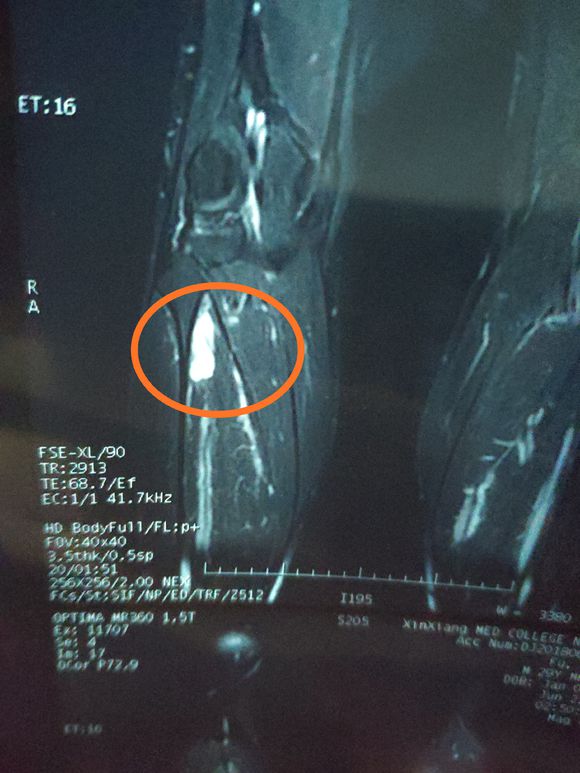

身心俱疲斗争 02019-02-22 患者家属女儿14岁,明天做截肢手术。医生让从髋关节处截,想保留个七八公分。问问大神们髋关节以下留七八公分能用常规的假肢吗? ...

一路向北 02019-01-28 患者家属我孩子今年15岁,年初查出骨肉瘤,左腿关节处,化疗5次做载肢,手术后伤口感染误了化疗,两个多月快三个月发生肺转,如今刚住...